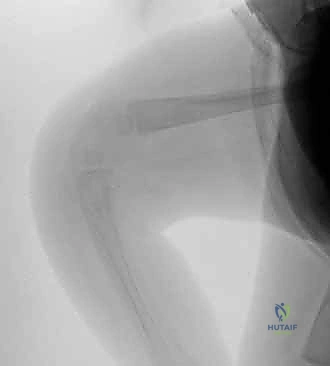

- التصوير بالأشعة السينية (X-rays): بالرغم من أن غضاريف الطفل حديث الولادة لا تظهر بوضوح في الأشعة، إلا أن الأشعة السينية ضرورية لتحديد العلاقة بين عظمة الفخذ وعظمة الساق، وتأكيد ما إذا كان الأمر مجرد فرط بسط (Subluxation) أم خلع كامل (Complete Dislocation).

- التصوير بالموجات فوق الصوتية (Ultrasound): أداة ممتازة وآمنة لتقييم الأجزاء الغضروفية غير المتكلسة في مفصل ركبة الرضيع وتحديد مدى انزياح المفصل بدقة.